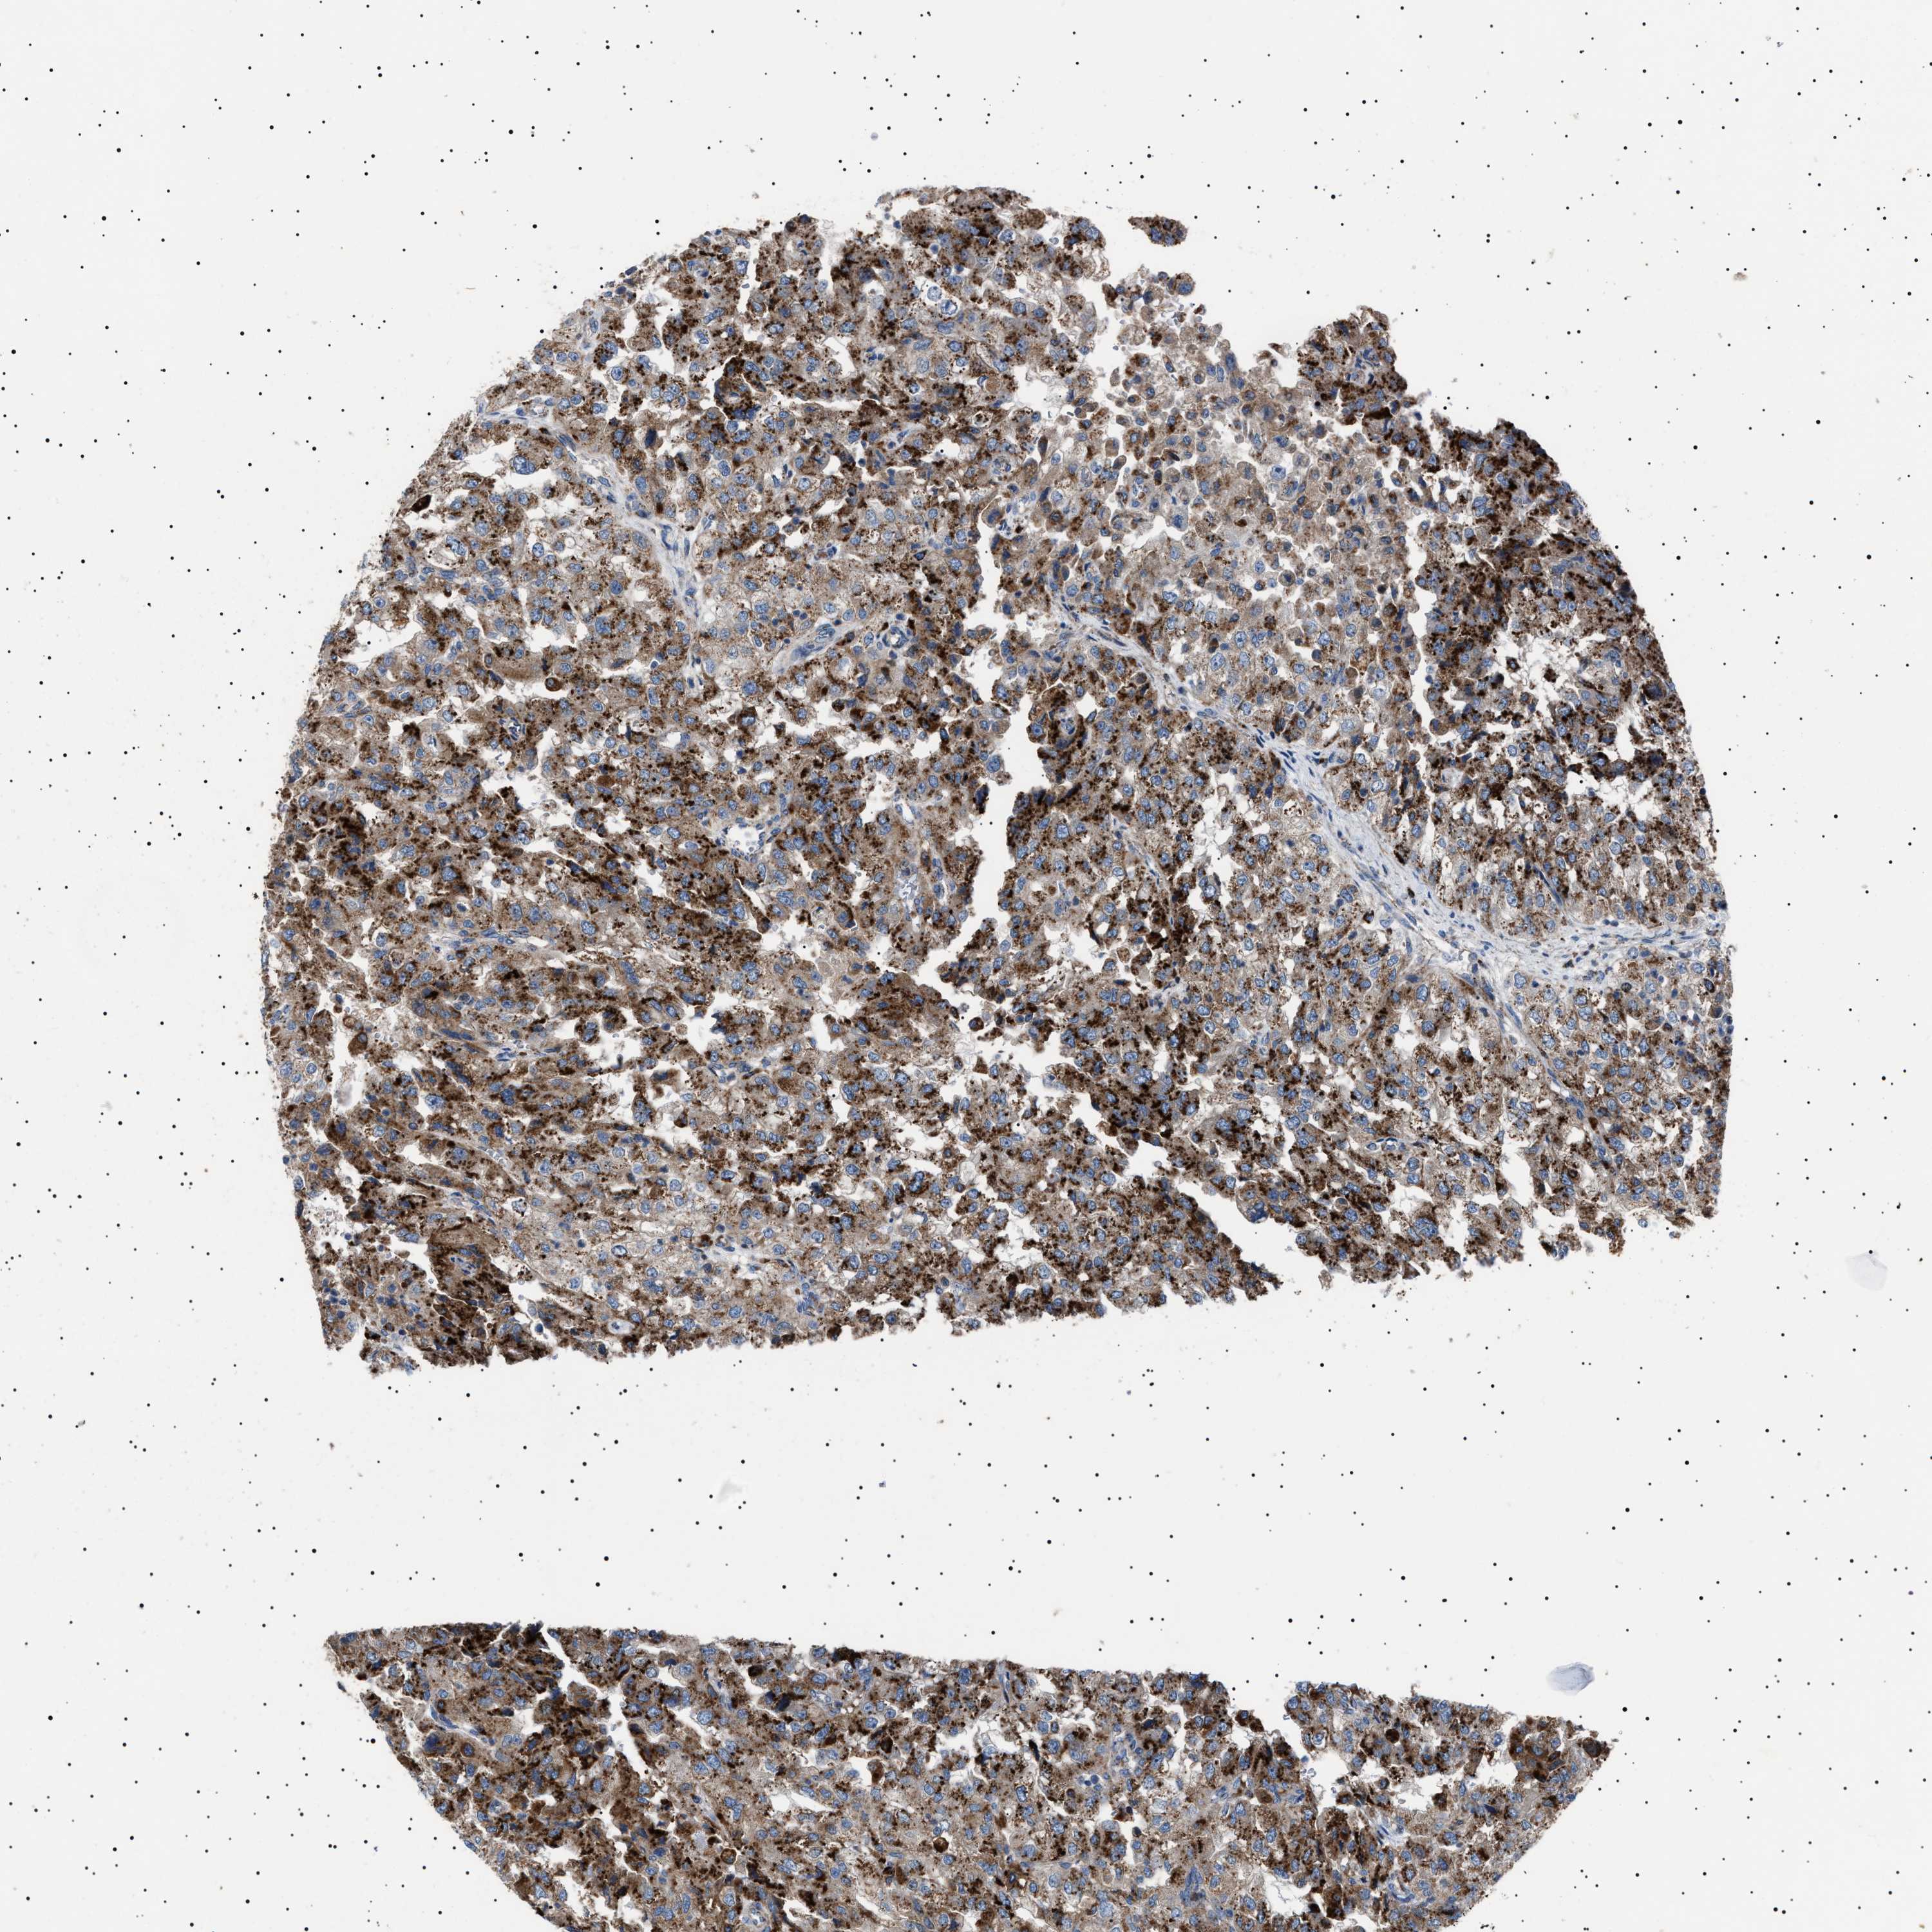

KIDNEY RENAL CLEAR CELL CARCINOMA (VALIDATION) - Interactive survival scatter ploti

The Survival Scatter plot shows the clinical status (i.e. dead or alive) for all individuals in the patient cohort, based on the same data that underlies the corresponding Kaplan-Meier plots. Patients that are alive at last time for follow-up are shown in blue and patients who have died during the study are shown in red.

The x-axis shows the expression levels (FPKM) of the investigated gene in the tumor tissue at the time of diagnosis. The y-axis shows the follow-up time after diagnosis (years). Both axes are complimented with kernel density curves demonstrating the data density over the axes. The top density plot shows the expression levels (FPKM) distribution among dead (red) and alive patients (blue). The right density plot shows the data density of the survived years of dead patients with high and low expression levels respectively, stratified using the cutoff indicated by the vertical dashed line through the Survival Scatter plot. This cutoff is automatically defined based on the FPKM cutoff that minimizes the p-score. The cutoff can be changed by dragging the vertical line or by entering a cutoff value in the square labeled "Current cut-off".

Under the Survival Scatter plot the p-score landscape (black curve; left axis) is shown together with dead median separation (red curve; right axis). Dead median separation is the difference in median mRNA expression between patients who have died with high and low expression, respectively. It is calculated as follows: median FPKM expression of dead patients with high expression - median FPKM expression of dead patients with low expression. This is intended to aid the user in visually exploring custom cutoffs and the associated p-scores and dead median separation.

Individual patient data is displayed and can be filtered by clicking on one or more of the category buttons on the top of the page. Categories describing expression level and patient information include: high, low, alive, dead, female, male and tumor stages. The scale of the x-axis can be toggled between linear and log-scale by clicking on the "x log" button. Mouse-over function shows TCGA ID, patient information and mRNA expression (FPKM) for each patient.

& Survival analysisi

Kaplan-Meier plots summarize results from analysis of correlation between mRNA expression level and patient survival. Patients were divided based on level of expression into one of the two groups "low" (under cut off) or "high" (over cut off). X-axis shows time for survival (years) and y-axis shows the probability of survival, where 1.0 corresponds to 100 percent.

NEU1 is not prognostic in Kidney Renal Clear Cell Carcinoma (validation)

Best expression cut offi

Based on the FPKM value of each gene, patients were classified into two groups and association between prognosis (survival) and gene expression (FPKM) was examined. The best expression cut-off refers the FPKM value that yields maximal difference with regard to survival between the two groups at the lowest log-rank P-value. Best expression cut-off was selected based on survival analysis .

When clicking on this number, the vertical dashed line indicating cut-off, the interactive survival plot, and the Kaplan-Meier curve will be adjusted to show results based on the best expression cut-off.

: 1.09

P scorei

Log-rank P value for Kaplan-Meier plot showing results from analysis of correlation between mRNA expression level and patient survival.

N/A

TCGA RNA samplesi

RNA-seq data is reported as average FPKM (number Fragments Per Kilobase of exon per Million reads), generated by the The Cancer Genome Atlas (TCGA) .

Normal distribution across the dataset is visualized with box plots, shown as median and 25th and 75th percentiles. Points are displayed as outliers if they are above or below 1.5 times the interquartile range. FPKM values of the individual samples are presented next to the box plot.

Average pTPM 1.4

Number of samples 100